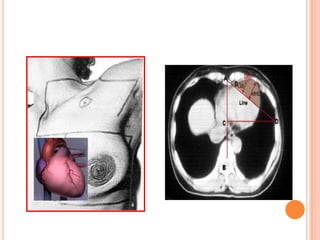

 A pectoralis major

muscle

 B axillary lymph

nodes: levels I

 C axillary lymph

nodes: levels II

 D axillary lymph

nodes: levels III

 E supraclavicular

lymph nodes

 F internal

mammary lymph

nodes